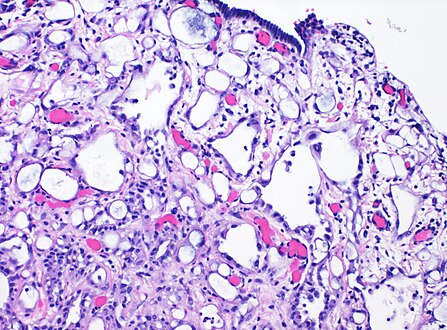

| High-magnification micrograph of an adenomatoid tumor. H&E stain. | |

High magnification of the same case, showing the typical[10] features of tubular spaces of varying size composed of flattened cells resembling endothelium.